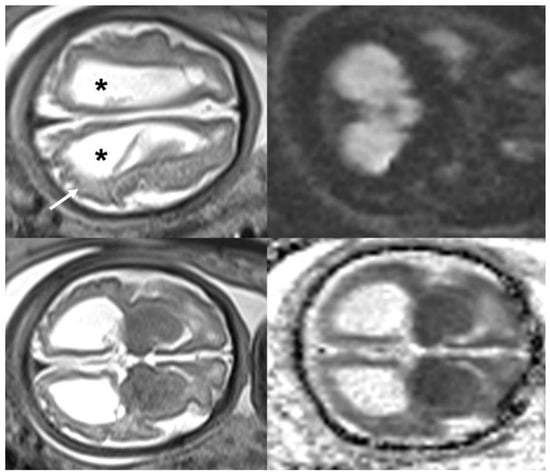

- Araujo Júnior, E.; Carvalho, F.H.; Tonni, G.; Werner, H. Prenatal imaging findings in fetal Zika virus infection. Curr. Opin. Obstet. Gynecol. 2017, 29, 95–105. [Google Scholar] [CrossRef] [PubMed]